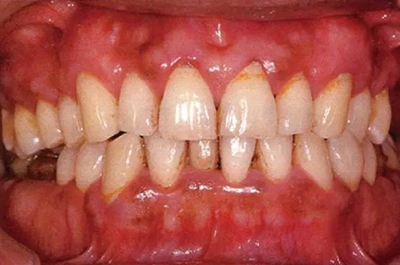

患牙齦炎的牙周組織的臨床圖像

22歲男性牙齦炎的臨床圖像

22歲男性,抽煙(1天約15根,煙齡5年)。刷牙狀態(tài)不佳。抽煙者特有的纖維性牙齦,未見發(fā)紅、腫脹。探針觸診,所有部位均出血。X線牙片未見骨吸收,診斷為牙齦炎。

14歲男性牙齦炎的臨床圖像

14歲男性。刷牙狀態(tài)不佳。整顎浮腫性發(fā)紅、腫脹且刺激出血。牙頸部有早期齲(白斑)。

26歲男性牙齦炎的臨床圖像

26歲男性。開口呼吸。混合有牙齦發(fā)紅、腫脹與纖維性肥厚。菌斑干燥牢牢黏住,刷牙難以刷掉。